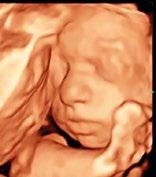

gáz-, kondenzációs kémények építése KÉMÉNYÉPÍTÉS Telefon: 06-20/533-6565, 06-20/314-4209 * 3104 Salgótarján, Nagymező út 11/A. ( +36-20/236-3747, +36-20/451-3494  info@szigker.hu Építőanyag Kereskedelmi Bt. Szigetelne? Segítünk! A SZIGETELÉSEK KERESKEDŐJE Szigeteljen! Megoldjuk! (A készlet erejéig!) – Házának felmérésében (előzetes egyeztetés alapján, helyben). – Az Ön otthonára szabott egyedi árajánlat készítésében! – Állandó akciókkal! – Bőséges árukészlettel! BABAMOZI a legmodernebb 5D ultrahanggal! Nagy szeretettel várja két tapasztalt szonográfusunk a várandós kismamákat! Salgótarján, Március 15. utca 24. Telefonos előjegyzés: 06-20/532-0029 Nőgyógyászati, hasi és hüvelyi ultrahangot is végzünk! Dr. Al Ghaoui Nadim főorvos Tel.: 06-30/958-4303 Hétfőn és csütörtökön 16.00–19.00 óráig. Bejelentkezés: 06-70/206-3717, 32/420-111. NŐGYÓGYÁSZAT, GYERMEKNŐGYÓGYÁSZAT